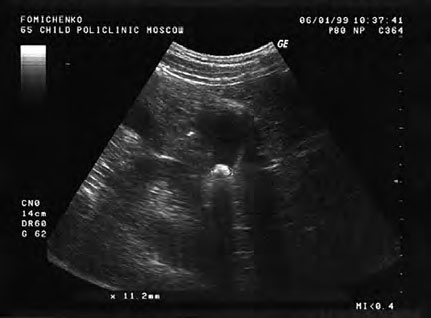

Данные последующего (третьего) ультразвукового исследования выявили практическое отсутствие эхо-признаков воспалительного процесса стенки желчного пузыря, сохранение его подвижности и уменьшение его максимального размера до 11,2 мм (рис. 29). Ультразвуковое исследование после пищевой нагрузки свидетельствовало о некоторой гиперкинетичности стенки желчного пузыря (сокращение объема желчного пузыря до 1/2 от исходного). Отмечено отсутствие динамики (по сравнению с предыдущими исследованиями) величины просвета печеночных желчных протоков. Сохранялась деформация стенок желчного пузыря, что несколько осложнило определение его объемов.

Рис. 29. Этапное (третье) ультразвуковое исследование желчного пузыря больной Т. Ф-ко